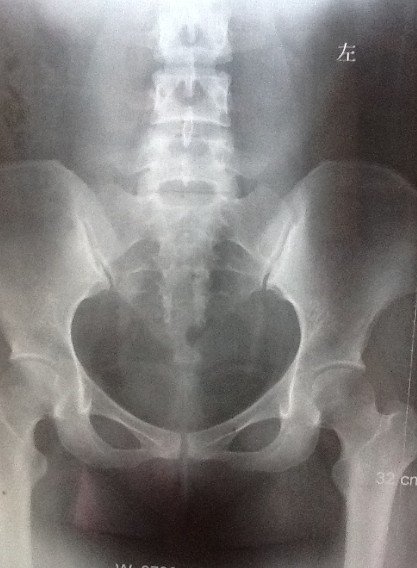

求助:帮我看看输卵管造影片吧

造影剂注入前 造影剂推入十几毫升时  造影剂完全推入  20分钟后的弥散照。 诊断:1.右输卵管炎          2.宫腔粘连         3.盆腔粘连给医生看了后,说我宫腔粘连不明显,有一小缺口可能是气囊,并配了妇炎康复胶囊和妇康消炎栓,治疗炎症。主要还是说盆腔粘连比较严重,需要宫腹腔镜。本人曾有过阑尾炎开刀史和胆囊炎开刀经历,对宫腹腔镜很是畏惧。请专家帮我看看,我的盆腔粘连是不是很严重。不做宫腹腔镜是否还有怀孕机会?